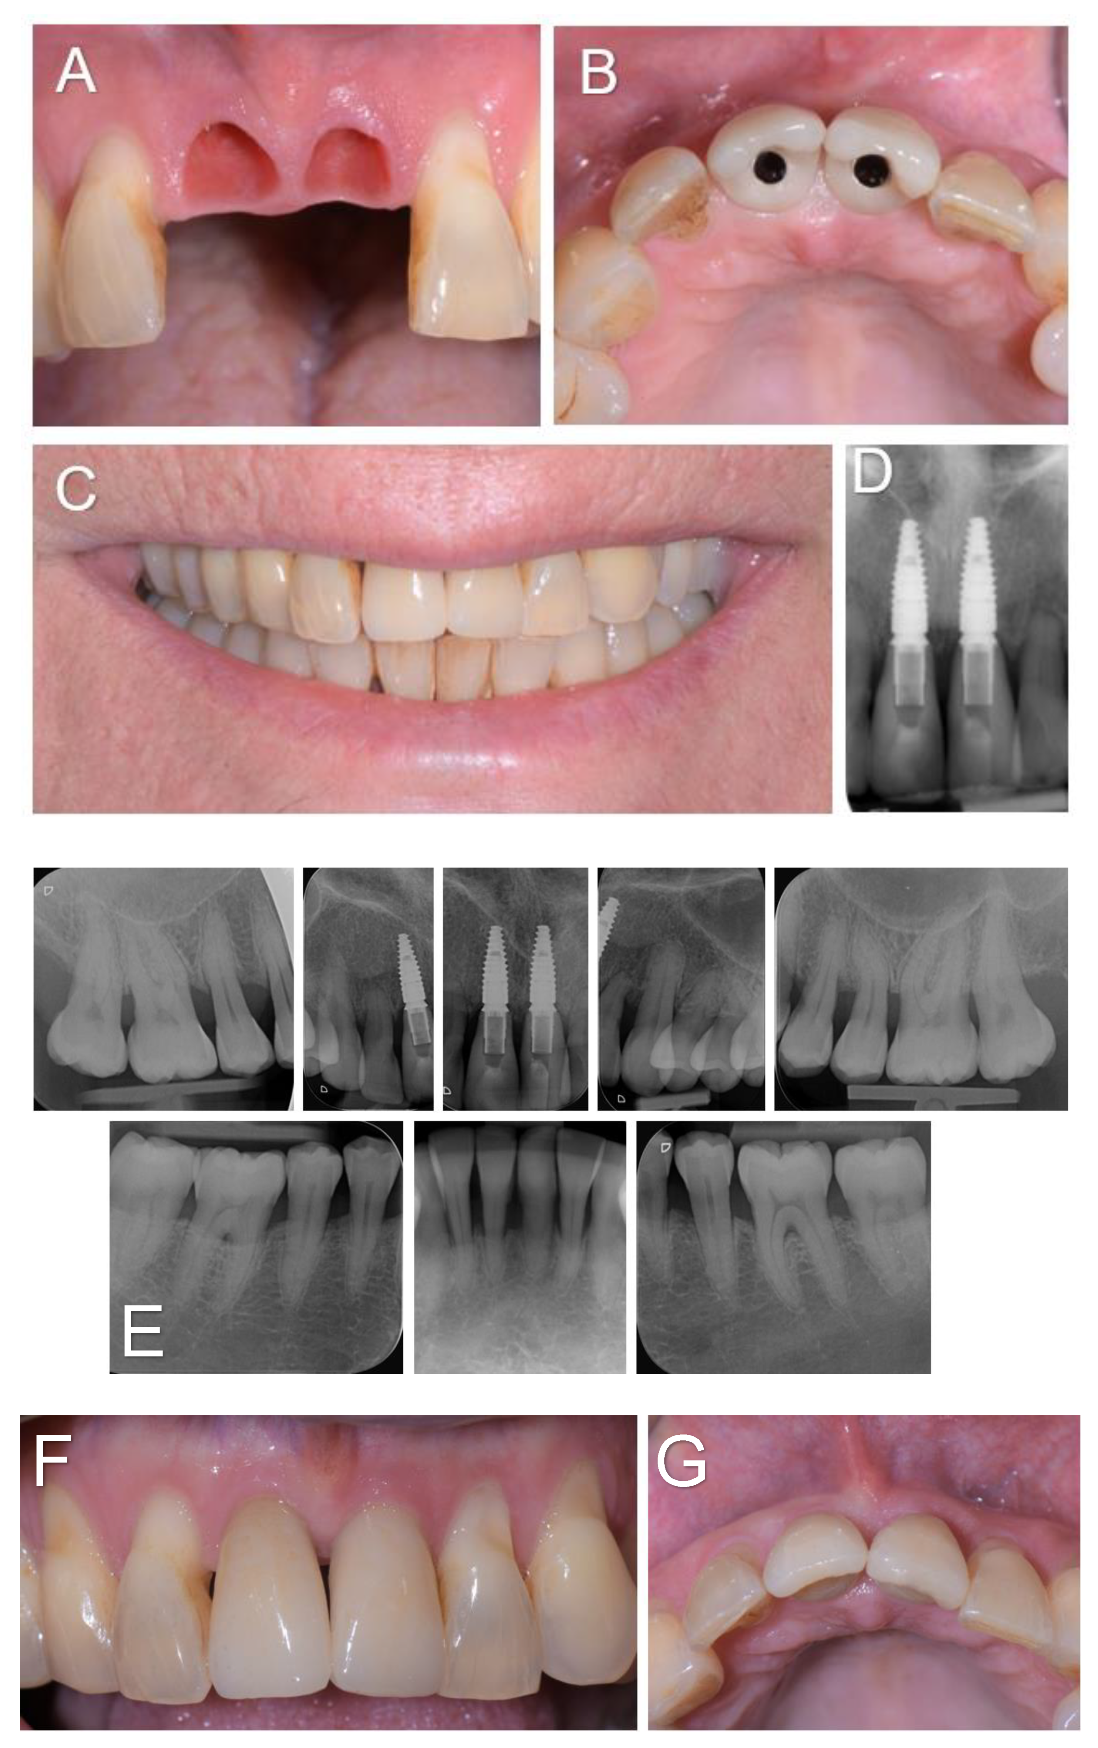

A 61-year-old woman was referred to the Oral Surgery and Implantology Unit of the University Hospitals of Geneva for treatment of edentulous sites after dental avulsions of teeth 11 and 21 following traumatic shock due to endotracheal intubation under general anesthesia performed to remove a laryngeal cyst. Past medical history was significant for pharyngeal dysesthesia and a supraglottic cyst. The dental history revealed that the patient had a history of chronic generalized periodontitis treated few years earlier. Clinical and radiological examination showed generalized bone loss especially at the edentulous sockets 11 and 21 and adjacent teeth 12 and 22.

Figure 1. Clinical view (A) and intra-oral radiographs (B) showing the initial clinical status after dental avulsions due to endotracheal intubation as well as the severe chronic periodontal disease.

Figure 3. (A-D). Soft tissues condition when the two screw-retained single-unit crowns (E-max. press) were delivered 3 months post-operatively (A, B), and clinical and radiographic examination at 3-year follow-up (C-G).